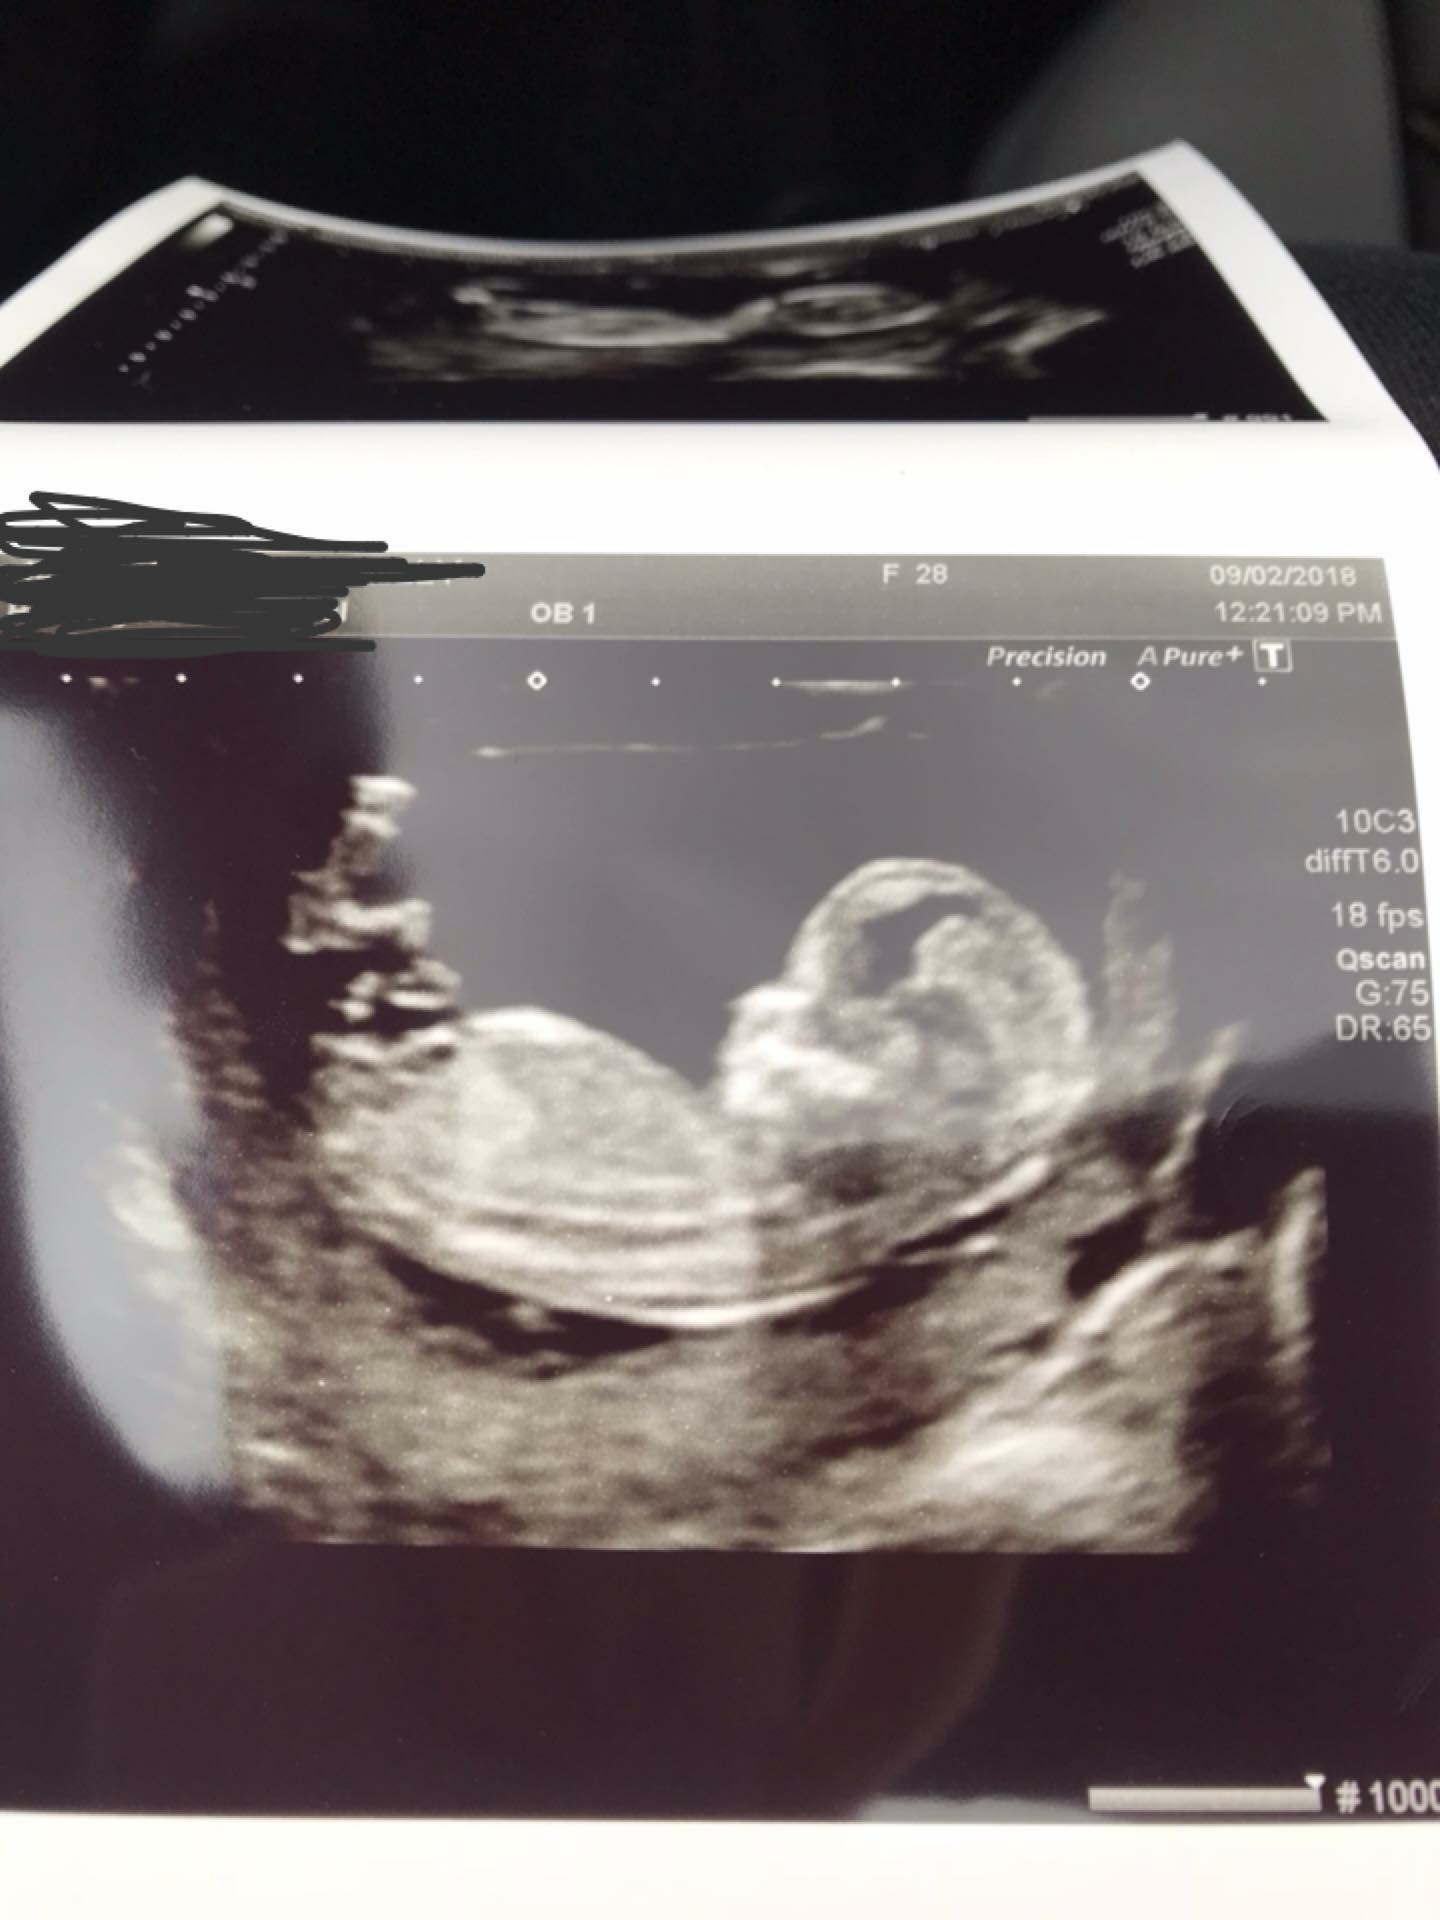

I’m 12w 5d here.

Looks girly

Girl guess from me. Do you have any other nub pics?

Congrats!! Looks very girly to me..FX!